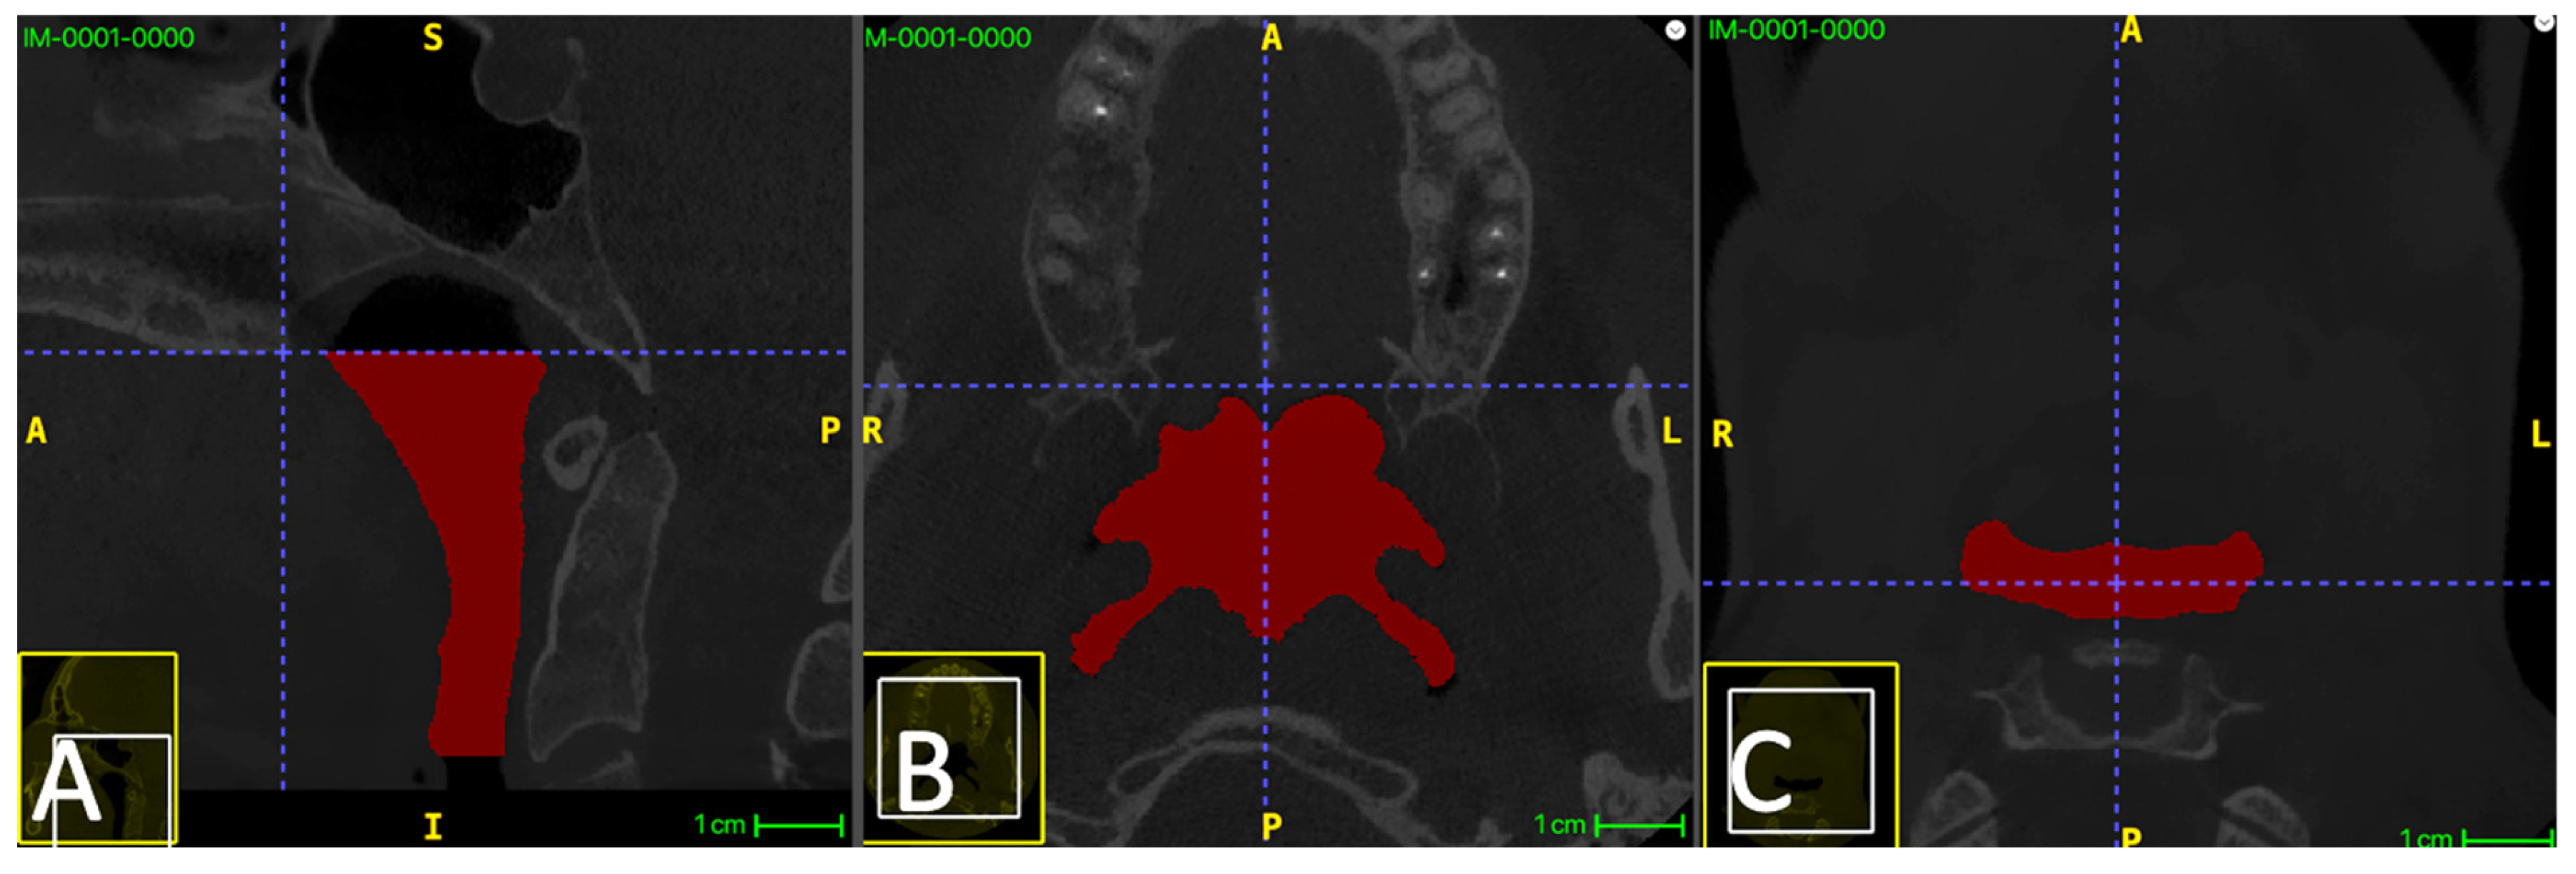

The airway lumen was segmented between Plane S and Plane I, bounded laterally and posteriorly by the pharyngeal soft-tissue walls and anteriorly by the posterior contour of the soft palate and tongue base (air–soft tissue interface). Air spaces outside the defined pharyngeal region (e.g., external air) were excluded by restricting segmentation to the ROI between Plane S and Plane I and by using connectivity-based region selection when applicable. The adopted boundaries are illustrated in Figure 1.

Figure 1. Definition of the segmented upper airway region. (A) Mid-sagittal CBCT view showing the superior boundary plane (Plane S) passing through posterior nasal spine (PNS) and parallel to the palatal plane, and the inferior boundary plane (Plane I) passing through the superior tip of the epiglottis and parallel to the palatal plane. The segmented pharyngeal airway lumen is highlighted in red. (B) Axial slice at the superior boundary (Plane S). (C) Axial slice at the inferior boundary (Plane I).